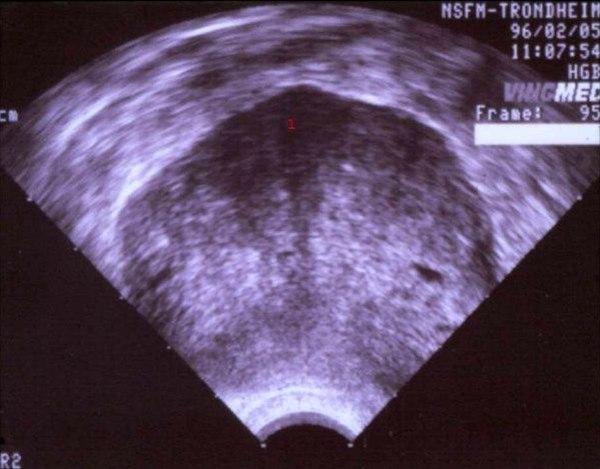

Sertoli-Leydig celle tumor

1. Tumormasse